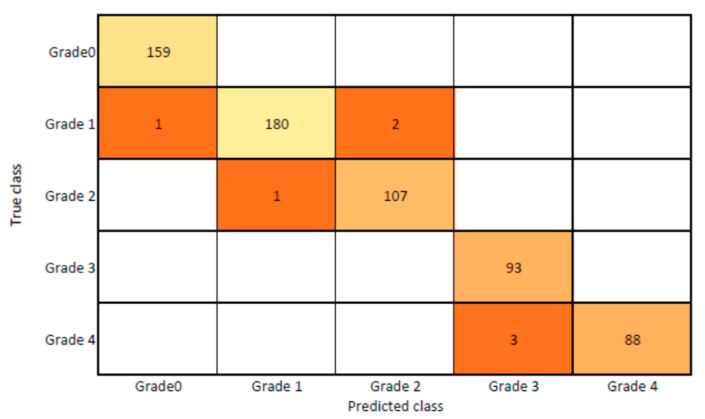

The presented model achieved 99.10% accuracy on the whole test set. The confusion matrix of the presented method is shown in Figure 8, and its performance is compared in detail to that of current methods in Table 5. In Figure 8, we examine the training and learning procedure as a whole to assess the planned activity’s success. Table 6 demonstrates the highest accuracy rate for classifying CBD grades zero–three–four knee joints. The knee joints with a CBD grade of one or two are the toughest to categorize. As can be seen in Figure 8, there is only a marginal amount of room for error when classifying knee joints as CBD Grades zero, three, or four. Knee joints that are classified as CBD Grades one or two have a small number of marginal misclassifications. In several circumstances, the proposed approach incorrectly estimated CBD Grade two as Grade one and vice versa. Joint space narrowing and bony spur development are significantly different in CBD Grade four knee joints. However, CBD-grade one knee joints show little change in JSN or osteophyte growth compared with the other classes. Types of knee RA and their intensity levels are shown in Figure 5. Table 8 and Figure 9 illustrate the JSN accuracy of the proposed and other state-of-the-art methods comparison.

In this study, we developed a deep learning model to automatically grade the severity of knee RA using a consensus-based approach. We compared the proposed work to prior strategies and found that it outperformed the competition. At the elementary level, notably in Grade one and Grade two, we found that our method differed from that of the medical professionals. We evaluated the presented work by comparing its results with similar existing studies. Compared with previously existing models, the presented work (a knee joint space narrowing diagnosis and class label) fares very well. It takes about 7 h of training to reach 0.6 k iterations. The outcomes of the presented methodology are shown in Table 9, which includes the outcomes of each CBD grade individually. Multiple metrics were employed to estimate the model’s performance, as indicated in Table 10. Figure 10 and Figure 11 depict the ROI curve for RA severity classification for both knees.

Figure 12 shows that the presented system outperformed other methods in terms of sensitivity (Se), specificity (Sp), precision (Pr), accuracy (Acc), and dice score (Ds), demonstrating deep learning’s capability. Figure 13 depicts the CBD grade outcome doughnut chart. In this research, the presented model increased overall ROI detection accuracy by up to 0.5 percent and improved classification accuracy by up to 1.18 percent. The proposed model is more dependable as a result of the detailed knee JSN characteristics. The improvement was satisfactory, and we agree with the observation that the AP view has a significant portion of the information necessary to assess the severity of knee RA with the CBD grading system. The CBD score is often examined using the AP view alone. Table 6 presents a comparison of the output of the proposed methodology with that of other methods that are currently in use. R K Ahalya et al. (2022) obtained Se of 0.9491, Sp of 0.9408 Pr of 0.9213, Acc of 0.9551 and Ds 0.8991; Uma Ramasamy et al. (2022) achieved Se of 0.8891, Sp of 0.8982, Pr of 0.8844, Acc of 0.9012, and Ds of 0.8923; Shawli Bardhan et al. (2021) obtained Se of 0.9785, Sp of 0.9561, Pr of 0.9713, Acc of 0.9864, and Ds of 0.9231; Rabbia Mahum et al. (2021) achieved Se 0.9815, Sp of 0.9789, Pr of 0.9896, Acc of 0.9714, and Ds of 0.9795; Kristine et al. (2022) obtained Se of 0.9012, Sp of 0.9101, Pr of 0.8915, Acc of 0.9211, and Ds of 0.9117; Shawli Bardhan et al. (2020) achieved Se of 0.8889, Sp of 0.8541, Pr of 0.8114, Acc of 0.8671, and Ds of 0.8781; and Sujeet More et al. (2022) obtained Se of 0.9622, Sp of 0.9771, Pr of 0.9831, Acc of 0.9685, and Ds of 0.9121. Our active deep CNN model acquired a knee joint identification accuracy of 98.97% and a knee RA severity classification accuracy of 99.10% using the presented methodology. This model also gives superior performance to handmade features. The active deep CNN model that we have presented and the pre-trained domain adaptation models that are employed in our system produce improved prediction accuracy outcomes for the five classes of knee RA that were experimentally determined.